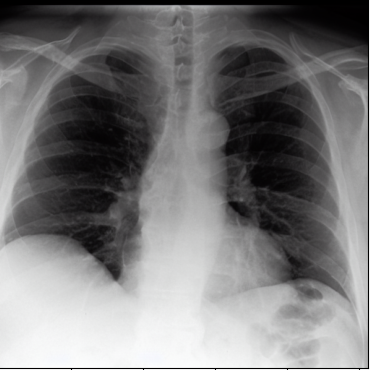

Figure 2: Fusion process applied to an image from the tail class Tortuous Aorta (a.1) and one of its neighbor images from the head class Atelectasis (b.1). (a.2) and (b.2) are channelwise Maximum Intensity Projections of the sparse vectors obtained from (a.1) and (b.1) respectively. In (a.3) and (b.3), we use EigenCAM to find attention maps for each sparse vector and define binary masks (yellow is one and dark purple is zero) using τh=τl=0,4formulae-sequencesubscript𝜏subscript𝜏𝑙04\tau_{h}=\tau_{l}=0,4 as thresholds. We combine the masked sparse vectors into (c) and decode the vector into a fused image (d). Finally, we apply five inference steps in (e) to obtain a less noisy image.

The method was tested by generating tail classes of a sampled version of MIMIC-CXR-LT 2023 [16, 13], a multilabel multiclass long-tailed dataset of chest X-rays. Our reduced sample version has only five head classes and five tail classes.